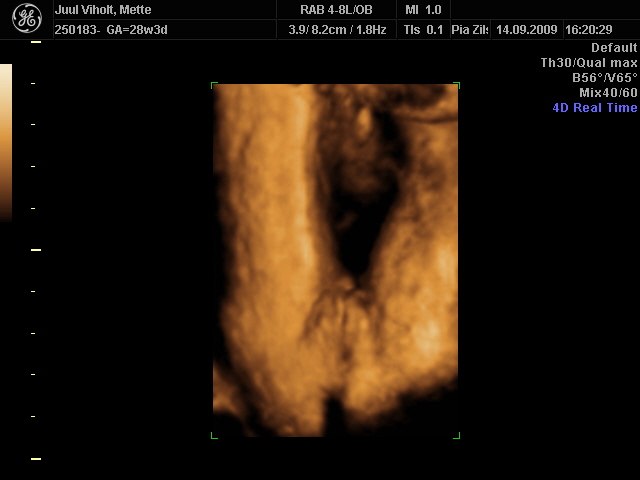

Jeg vedhæfter lige 3D billede af min datter i uge 29. Så kan du se at kønsdelene er "meget" hævede - hvorfor det kan ligne en dreng.

En pige.